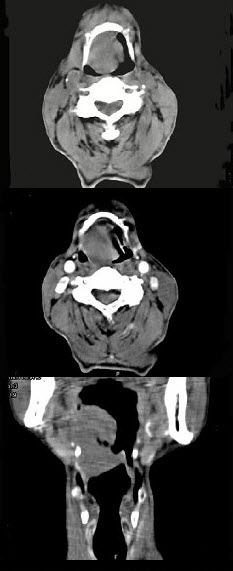

男,74岁,咽喉部不适一年余,近两三个月咽喉疼痛,吞咽困难,CT如图所示,最可能诊断是()。

A、喉癌

B、会厌癌

C、声带癌

D、声门下区癌

E、跨声门型癌

正确答案:

B